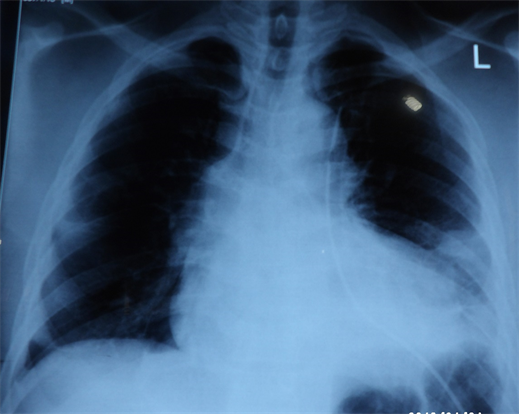

Extended Focused Assessment with Sonography for Trauma (eFAST) was positive for left pleural space collection but negative for haemoperitoneum and haemopericardium. Diagnosis of chest trauma with left Pneumohaemothorax and multiple facial abrasion secondly to road traffic accident was made. So the patient was started with Intravenous fluid with a litre of Ringers lactate run fast, antibiotics, i.v cefuroxime 1.5 g start, and blood was taken for complete blood count, chemistry, kidney and liver function tests. Serum was also group-match against 4 units of blood. Antitetanus prophylaxis, i.m tetanus toxoid, ATS 1500 UI doses given and a size 36 FG chest tube was passed under local infiltration draining immediately 1200 mls of blood and the tube was clamped. Another 700 mls of blood was drained after an hour when the clamp was released, therefore a massive haemothorax diagnosis was made and the patient was then prepared for surgery. Chest x-ray after the chest tube insertion showed a left lower opacification with pleural effusion as shown in Figure 1. As patient being prepared for surgical exploration, he suddenly became totally blind, so an urgent CT head scan was requested and the neurosurgeons and ophthalmology surgical teams consulted. However, he had remained stable after two units of whole blood transfusion. The CT scan of the Head showed basal skull fracture with bilateral occipito-parietal, non-hemorrhagic contusions as shown in Figure 2 and the neurosurgeons recommended a conservative management upon review. However after

Figure 1. Chest x-ray showing left lower opacification with a chest tube in-situ.

Options for radiological imaging of the heart and pericardium in acute trauma include ultrasonography in the form of FAST (Focused Assessment with Sonography in Trauma) or echocardiography, chest radiography and CT scan. FAST has been reported to have a high sensitivity (97% - 100%) in identifying pericardial injuries [11] . Chest x-rays have limited potentials to identify pericardial or cardiac injuries. However, it is particularly useful in identifying associated complications such as hemothorax, pneumothorax, pneumomediastinum or pneumopericardium [11] . Most commonly identified radiological features seen on chest x-ray are deviation of pericardial shadow and pneumopericardium [5] . CT scan of the chest is the preferred radiological technique in diagnosing traumatic pericardiotomy which characteristically shows as empty pericardial sac sign, pneumopericardium or pericardial displacement [7] [10] . Despite these available radiologic interventions, the non-specificity of clinical signs and symptoms suggestive of traumatic pericardiotomy and the severe hemodynamic instability result in prioritization of surgical exploration as against further radiological evaluation hence an in intra-operative diagnosis [7] [12] . The initial diagnostic imaging done for our patient was the EFAST, because he was unstable and this was able to pick the haemothorax. A chest x-ray was done after patient’s stabilization including the passage of a tube thoracostomy.